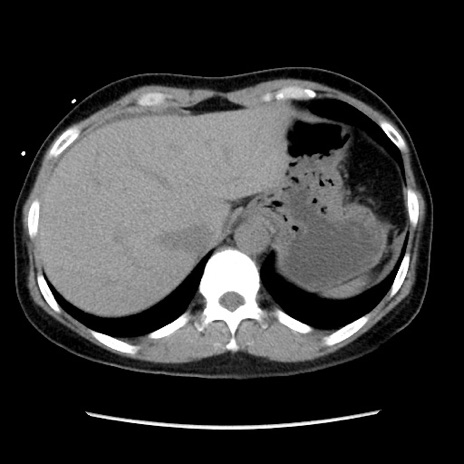

冠状断像

【症例】 50歳代女性

【主訴】 腹痛

【現病歴】前日生レバーを食べた。今朝に排便あり。 昼前に突然発症の腹痛を生じ、当院救急外来を受診した。

【身体所見】 意識清明、腹部:平坦、軟、下腹部やや左を中心に圧痛・反跳痛あり、筋性防御あり

【データ】WBC 7800、CRP 0.07